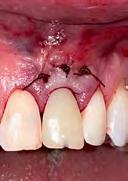

5. Image 5a: A 15mm x 20mm x 3mm Geistlich Fibro-Gide® collagen matrix was inserted into the supra-periosteal pocket, with the coronal portion positioned to cover the facial bone crest. Image 5b: The provisional crown was placed, and the facial mucosal flap was coronally advanced to cover the Geistlich Fibro-Gide® collagen matrix.

6. Images 6a & 6b: 2-week post-operative follow-up.